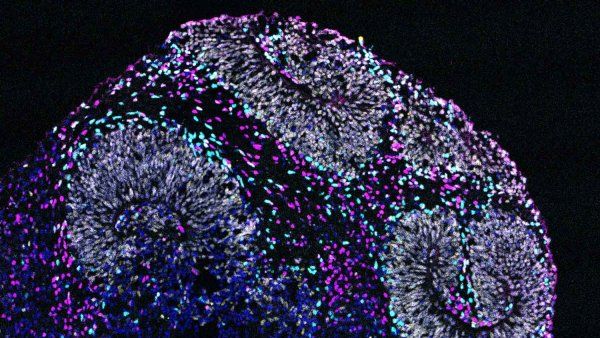

The Road to Rejuvenation